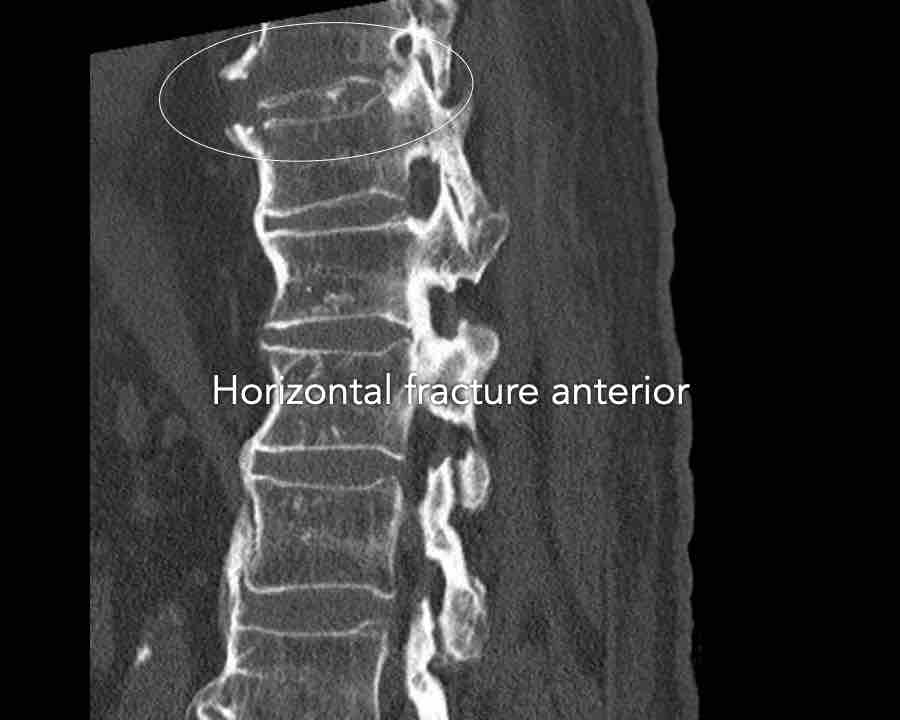

B3 Extension distraction injury

Hyperextension can result in distraction of the anterior tension band, which is formed by the vertebral bodies, the anterior and posterior longitudinal ligaments and the intervertebral disc.

These injuries can be difficult to detect since patients are scanned in the supine position laying on their back, which may obscure the anterior distraction.

However, these injuries mainly occur in patients with a rigid spine as a result of osteoarthritis, DISH or Ankylosing Spondylitis (SpA).

Stay persistent when examining a patient with a rigid spine until you have found the B3 injury.

Extension distraction is characterized by:

- Distraction of the tension band on the anterior side.

- Any horizontal or oblique fracture line through vertebral bodies anteriorly with separation on both sides.

- Widening of intervertebral disc space.

Scroll through images.

What are the findings?

Findings

- C injury? No.

- Signs of a rigid spine?

Yes, so be aware of potentially very subtle B3 injury. - A subtle fracture on the anterior vertebral body is seen (arrows).

Conclusion

Injury type B3.